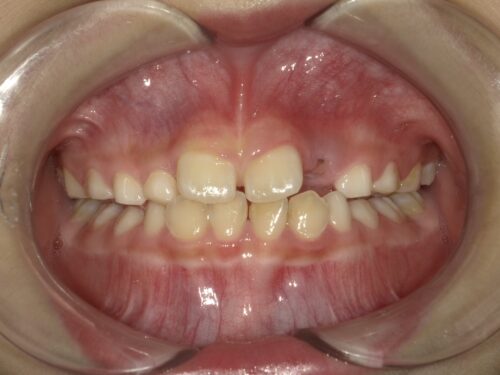

約半年間の装置の使用とトレーニング後の写真です。

前歯の噛み合わせは正常になりました。

隣の乳歯の噛み合わせも改善されています。

歯並びは後戻りする可能性があるため、一定期間使用を継続し経過を見ていきます。